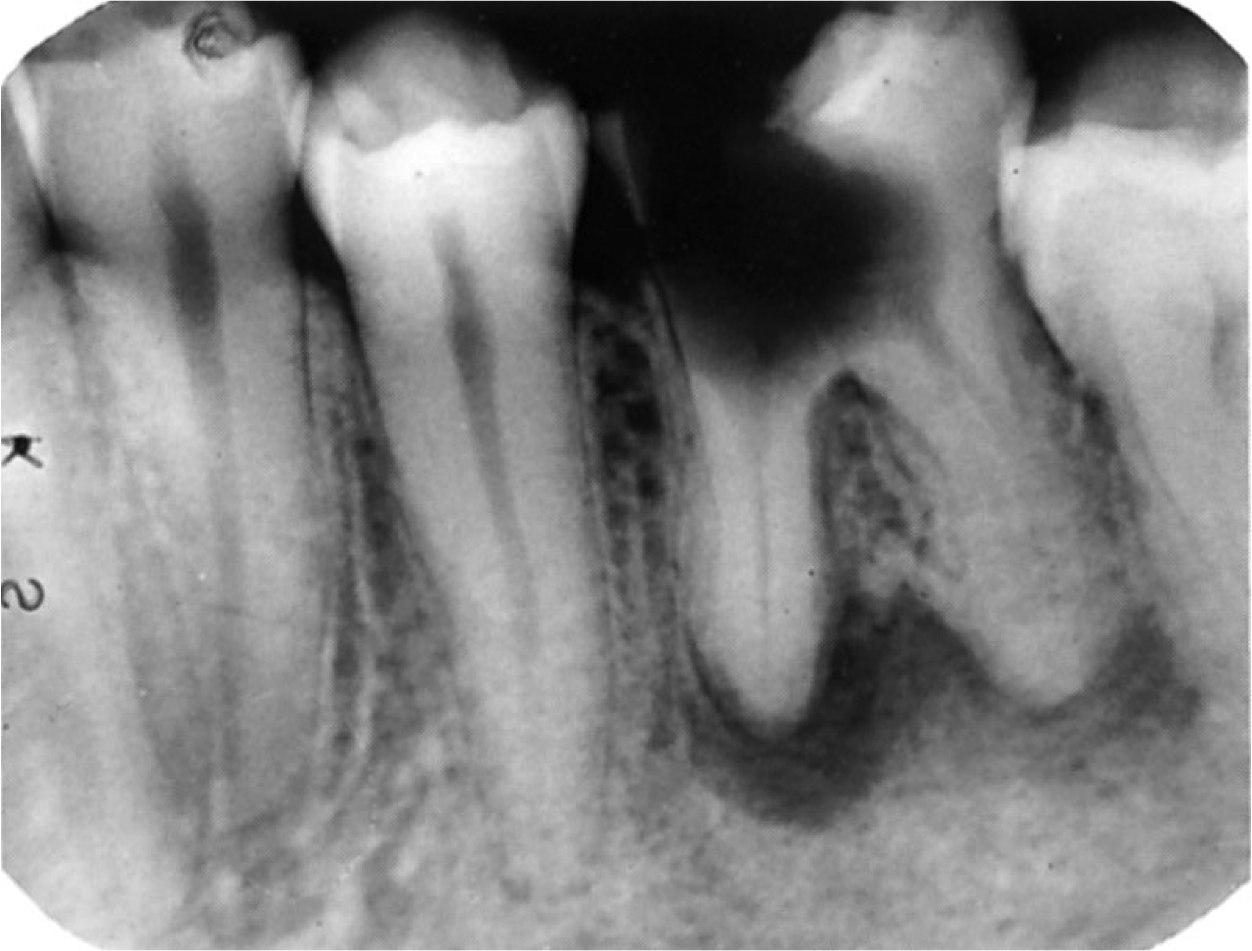

На фотографии показан рентген зуба с гранулемой вдоль корня моляра.

Диагностировать гранулему можно при помощи рентгенографического исследования, она возникает постепенно и является следствием такого кариозного осложнения, как периодонтит. Постепенно увеличиваясь, гранулема проявляется в виде припухлости десны и ее болезненности при пальпации. Если в гранулеме развевается гнойный процесс, то пациент ощущает пульсирующую зубную боль, зубная эмаль темнеет, появляются гнойные выделения.

Хроническое течение заболевания может быть бессимптомным, а в процессе прогрессирования болезни гранулема трансформируется в кисту. Гранулема является очагом хронической инфекции в организме и помимо потери зуба может дать серьезные осложнения на органы респираторного тракта и сердечно-сосудистую систему.

Консервативные методы терапии гранулемы не всегда позволяют сохранить зуб, при трансформировании ее в кисту чаще всего прибегают к хирургическому вмешательству.

На изображении показано расположение гранулемы у корня зуба.